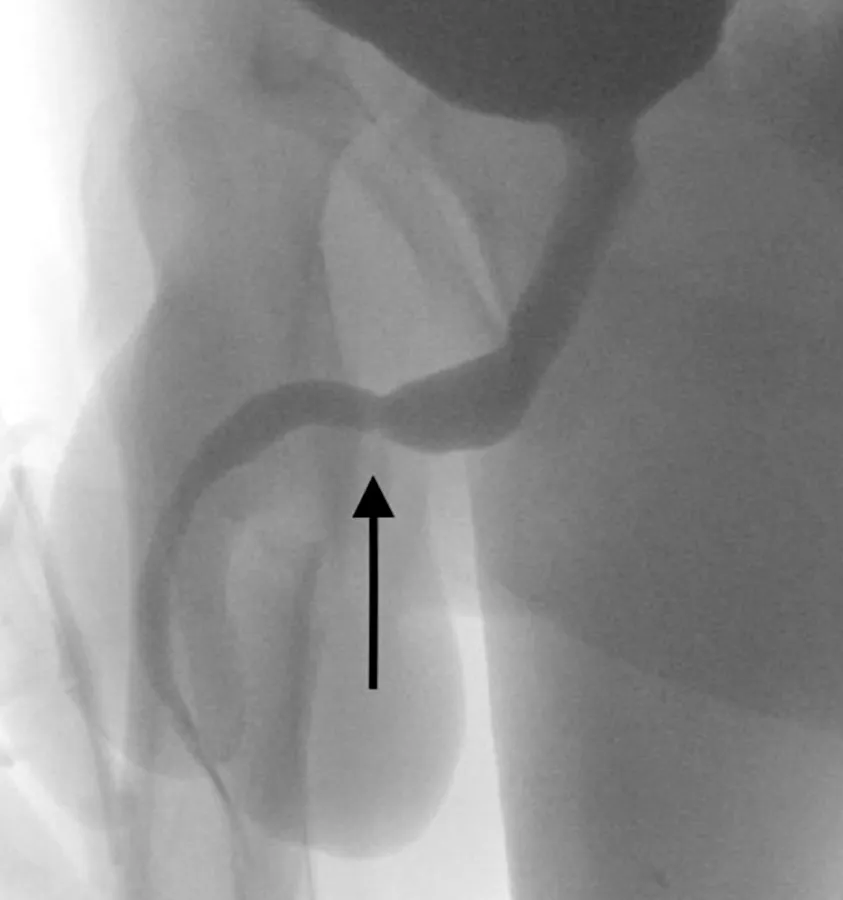

El curioso experimento no tuvo éxito: una vez que comenzó a orinar sangre, sus padres lo llevaron al hospital.Al examinar al joven, de 15 años, los médicos del University College Hospital de Londres vieron que el cable había quedado en su escroto, como si fuera un catéter electrónico. La radiografía reveló que tenía un verdadero nudo dentro de sus genitales.

Para extraer el nudo, los médicos tuvieron que hacer una incisión entre el pene y el ano del paciente.